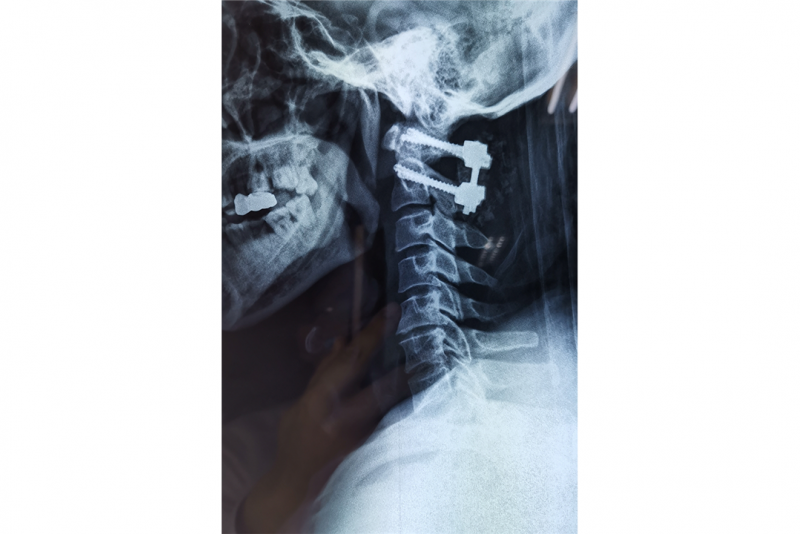

术后X光片

马先生及其家人充分信任烟台山医院脊柱外科,决定接受手术。当日,烟台山医院原副院长沈炳华主刀手术,术中脊髓诱发电位时刻监测神经功能变化。医生经后方切口显露环枢椎,置入环枢椎椎弓根根螺钉,球磨钻磨除C2右侧椎板,潜行减压寰椎后弓下缘,最大限度地保留了脊柱的后方结构。接着弧形切开硬脊膜,脑脊液泉涌而出,可见硬膜内髓外巨大肿瘤,肿瘤位于脊髓腹侧,肿瘤与腹侧硬脊膜紧密相连,剥离困难重重。“此时分离肿瘤犹如钢丝上舞蹈,稍有不慎后果不堪设想。”手术助手王磊升说。

手术中,沈炳华凭借其40多年的手术经验和娴熟的手术技巧小心巧妙地分离出肿瘤边界,完整切除了肿瘤,圆满完成了手术。王磊升说:“术中脊髓电生理监测波幅平稳,这表明手术操作对脊髓干扰轻微,预示着神经功能恢复良好。”术后,患者的肌力很快得以恢复,出院时行走自如,手术取得了最终的成功。